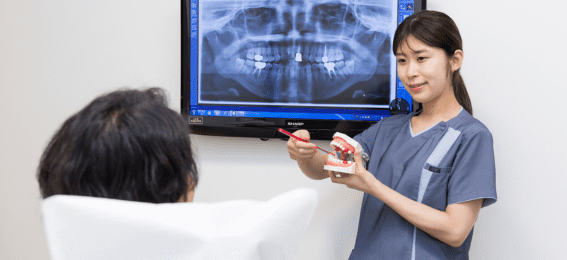

- 歯周病の治療パートナー:専門家との協働

歯周病の治療パートナー:専門家との協働

歯周病の治療を導く:一般歯科医と歯周病専門医

歯周病の早期発見と治療は、一般歯科医の役割の一部です。私たちは患者の歯と口腔の健康全体を管理し、定期的なクリーニングと検診を行うことで、歯周病の早期発見に貢献します。しかし、歯周病が進行し、複雑な治療が必要になった場合、歯周病専門医(歯周病専門医)の力を借りることもあります。彼らは長期的な治療プランの設計と実行、高度な手術技術を提供します。

歯の健康の守護者:歯科衛生士の役割

歯科衛生士は、口腔ケアの最前線で活躍するプロフェッショナルです。定期的なクリーニングを行い、歯周病の初期段階であるジンギバイティスの兆候を探します。さらに、歯科衛生士は適切なブラッシングやフロッシングの方法を指導し、口腔衛生製品の選択についてアドバイスを提供します。これにより、患者は自宅でのケアを最適化し、歯周病の発症を防ぐことができます。

専門的な視点で治療を最適化:専門的なケアとセカンドオピニオン

特に重度の歯周病を抱える場合、専門的なケアを受けることで、より効果的な治療を実現できます。歯周病専門医は、進行した歯周病の治療に特化した知識と技術を持っています。さらに、治療の進行や効果について不確かな場合、セカンドオピニオンを求めることは、あなたの治療計画を最適化し、自信を持つための重要なステップとなります。

歯周病は複雑な病状であり、その管理には多角的なアプローチが必要となります。そのため、一般歯科医、歯周病専門医、歯科衛生士など、各専門家と連携して最適な治療プランを作成し、継続的なケアを受けることが大切です。健康な口腔を保つために、信頼できる専門家のアドバイスを活用しましょう。